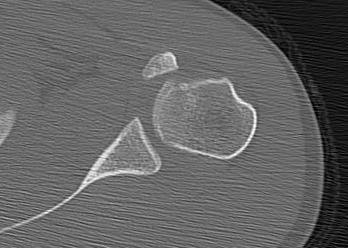

proximal humerus fracture Background ORIF with locking plate Arthroplasty Greater tuberosity fractures Lesser tuberosity fractures / avulsions Book traversal links for Proximal humerus fractures ‹ Pectoralis Major Tears Up Background ›